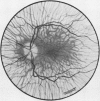

Intermediate sex-linked inheritance.